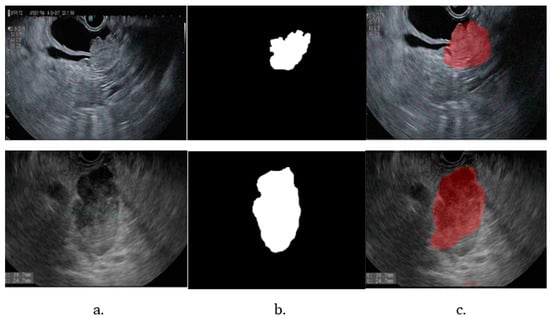

The repeated training and the different stages of tumor segmentation models are represented in Figure 5. The bile duct segmentation model-generated contour over the original image is shown in Figure 6.

Figure 6. Bile duct pathway segmentation. (a) Original image; (b) binary mask; (c) testing image.